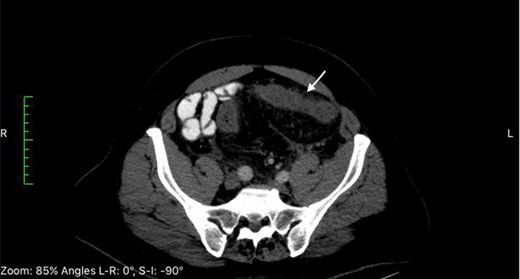

CT of the abdomen at time of admission reveals thickening of the sigmoid colon (white arrows).

A 63-year-old Middle-Eastern man developed sudden onset of lower abdominal pain and non-bloody diarrhea. At time of presentation there was no report of fever, chills, nausea or emesis. The patient was overall healthy except for a history of benign prostatic hyperplasia and degenerative osteoarthritis of the knees, which he treated for several months with a Chinese herbal supplementation. The past surgical history was significant for tonsillectomy and inguinal hernia repair. The patient had received a course of oral ciprofloxacin due to worsening of his diarrhea. He was admitted to the hospital and laboratory results were significant for an elevated C-reactive protein at 140 mg/L. Computed tomography (CT) scan revealed left sided colitis involving the sigmoid and descending colon (Fig. 1). Serosal irregularity and pericolic inflammation change with mesocolic vascular congestion and hyperemia. Colonoscopy showed edema and erythema without gross ulceration. An additional course of intravenous ciprofloxacin and metronidazole was unsuccessful in resolving the symptoms leading to the administration of ertapenem and azithromycin by the treating gastroenterologist. Subsequent stool studies were positive for Entamoeba histolytica prompting a full course of oral tinidazole. With worsening of the patient’s symptoms, a second CT scan performed 12 days later demonstrated interval progression of the colitis to the distal transverse colon with free intra-abdominal fluids (Fig. 2). Repeat colonoscopy to assess for inflammatory bowel disease showed diffuse edema and erythema without deep ulceration. Biopsies revealed non-specific severe colitis. Despite bowel rest with total parenteral nutrition and the various intravenous and oral antibiotics, the patient continued to deteriorate prompting an extended left hemicolectomy with end transverse colostomy and a low Hartmann’s rectal pouch 26 days after initial presentation. Examination of the 75 cm specimen revealed macroscopic features of ischemia with indurated brown-reddish bowel wall and bulky hardened mesenteric fat tissue (Fig. 3). Gross inspection of the inflamed mucosa revealed a fibrinous layer. Histopathologic assessment showed inflammation and fibrosis of the mucosa, especially of the lamina propria with rarefaction of the crypts. Proliferation of small vessels was visible in the lamina propria, the submucosa and the pericolic fat. Moreover, some vessels showed a fibromyxoid wall-thickening. Elastic van Gieson (EvG) stains revealed massive changes in venous structures with hyperplasia of the cellular and matrical mass in the initmal layer leading to subtotal occlusion of the venous lumens. Histology identified focal secondary thrombosis. Some lymph nodes were rich of plasma cells with a dilated sinus with ectasia of the lymph vessels. The findings were consistent with IMHMV.